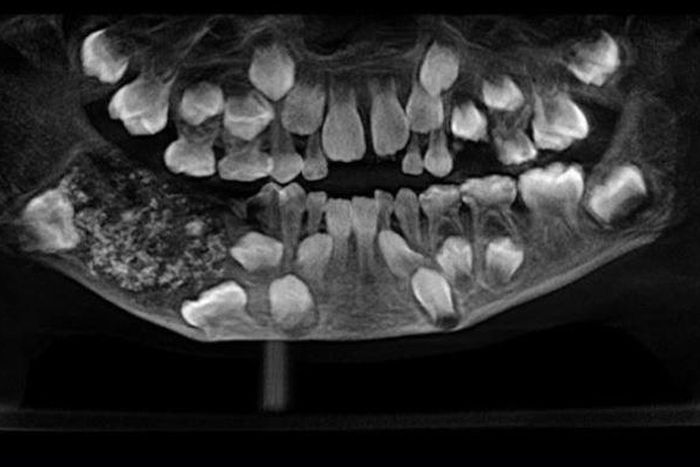

A team of doctors at the Oral and Maxillofacial Pathology headed by Dr. Prathiba Ramani conducted a scan and spotted a sac embedded in his lower jaw filled with “abnormal teeth.”

“There were a total of 526 teeth ranging from 0.1 millimeters (.004 inches) to 15 millimeters (0.6 inches). Even the smallest piece had a crown, root and enamel coat indicating it was a tooth,” Dr. Prathiba Ramani is quoted as saying.

She explained that the boy was suffering a very rare condition called compound composite odontoma whose cause is not yet known.